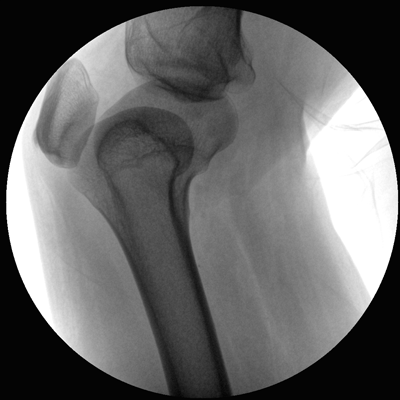

小巧輕便 超凡靈動(dòng) PLX C1116

●全數(shù)字化百萬(wàn)像素影像系統(tǒng),圖像清晰